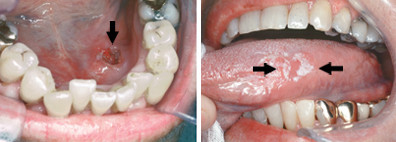

Oral Cancer

Oral cancer is cancer anywhere in the front of the mouth. It includes any cancer on the lips, tongue, inside surface of the cheeks, hard palate (the front of the roof of the mouth), or gums. Cancers in the back of the mouth, such as on the soft palate (the back of the roof of the mouth) or the back of the throat, are not considered oral cancer. Oral cancer is a type of cancer called squamous cell carcinoma, in which surface cells grow and divide in an uncontrolled way.